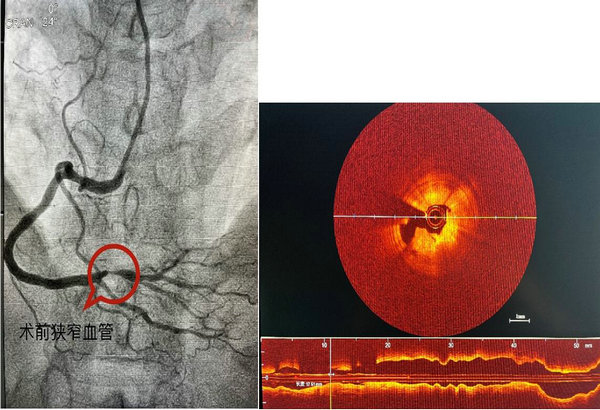

53岁的马女士家住讷河市,平素身体状况良好,无高血压、糖尿病病史,无吸烟、饮酒等不良嗜好,入院前一个月开始出现与活动劳累相关的胸骨后疼痛,伴有肩膀放射痛,持续数分钟后症状可逐渐缓解,为求诊治来到心血管内科三区。患者虽无明确冠脉病变易患因素,但心绞痛症状典型,入院后安排完善冠脉造影检查,结果显示患者右冠状动脉中远段99%狭窄,且病变局限,其余血管未见明显狭窄及钙化。结合患者实际情况,吴晓杰主任决定给予患者可吸收支架植入治疗,术前术后给予OCT检查,精准评估病变长度及管腔内径,OCT检查结果显示支架膨胀良好,无贴壁不良;管腔面积恢复满意,手术过程顺利。

术前影像图